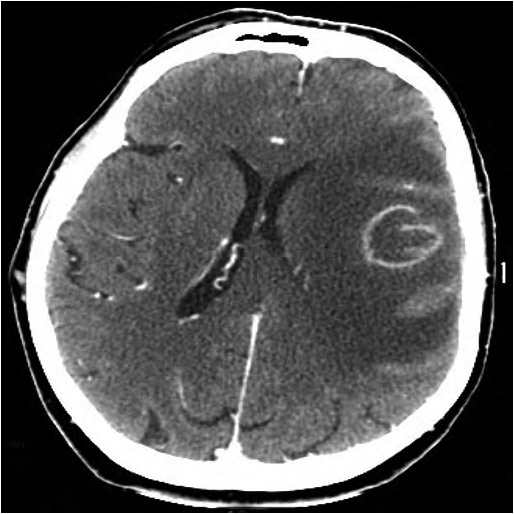

Через 1 мес пациентка доставлена бригадой скорой помощи в тяжёлом состоянии с нарушением уровня бодрствования до глубокого оглушения и грубым правосторонним гемипарезом (мышечная сила 2 балла). По данным МСКТ визуализированы 3 очага, кольцевидно накапливающие контрастное вещество, с выраженным перифокальным отёком. Учитывая результаты ИГХ, данное состояние расценено как множественные абсцессы головного мозга (рис. 3).

Рис. 3. МСКТ головного мозга пациентки Р. с контрастным усилением через 1 мес после операции.

Стрелки — объёмные образования обеих лобных и правой теменной долей с выраженным перифокальным отёком, кольцевидно накапливающие контрастное вещество.

Fig. 3. Contrast-enhanced brain MSCT image one month postoperatively.

Arrows — masses in both frontal areаs and in the right parietal lobe, with a ring contrast enhancement and significant perifocal edema.